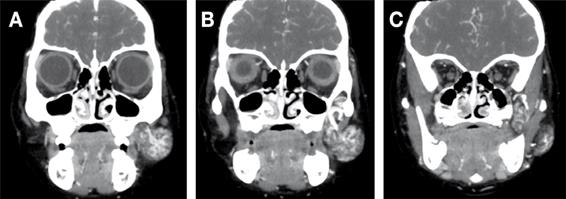

En la tomografía computarizada con contraste se evidenció en la región geniana izquierda, además de las regiones maseterina y pterigomaxilar, una lesión de densidad heterogénea, de predominio hipodenso, sugiriendo componente adiposo, de bordes definidos y delimitados por la fascia de los tejidos blandos vecinos, mide aproximadamente en su porción externa 32 x 17 x 29 mm (región geniano-maseterino) y su porción interna 18 x 13 x 28 mm (región pterigomaxilar), con un elemento vascular central importante, procedente principalmente de la arteria maxilar interna (Figura 3, 4 y 5).

Figura Nº4 . Vista coronal de TAC que muestra masa heterogénea en las regiones geniana y maseterina izquierdas, lateral al músculo buccinador que se extiende a la región pterigomaxilar (flecha).